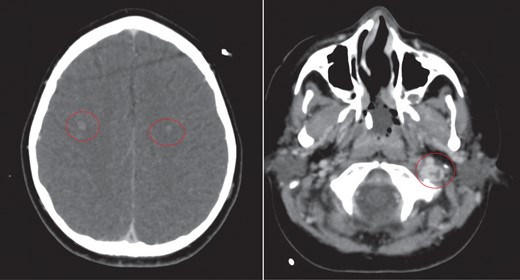

The cerebellar brain abscess was drained surgically, with pus sent for microscopy and culture. This returned gram negative coliform organisms and pus cells. The antibiotic therapy was modified to account for the new microbial sensitivities. The appearances of both the brain and chest improved over the next 10 days with complete resolution of the intracerebral abscesses and thrombosis (Fig. 8). There was a slower resolution of the chest. The patient was discharged from our institution after 16 weeks.

Eventual complete resolution of the brain abscesses and sinus/ IJV thrombosis.